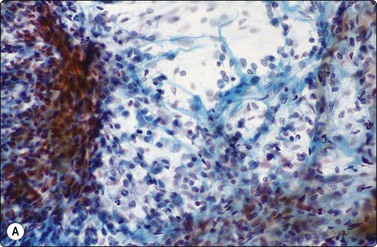

image

Fig. 8.1 Bronchiolar epithelium

Small sheet of regular glandular cells (Pap, HP).